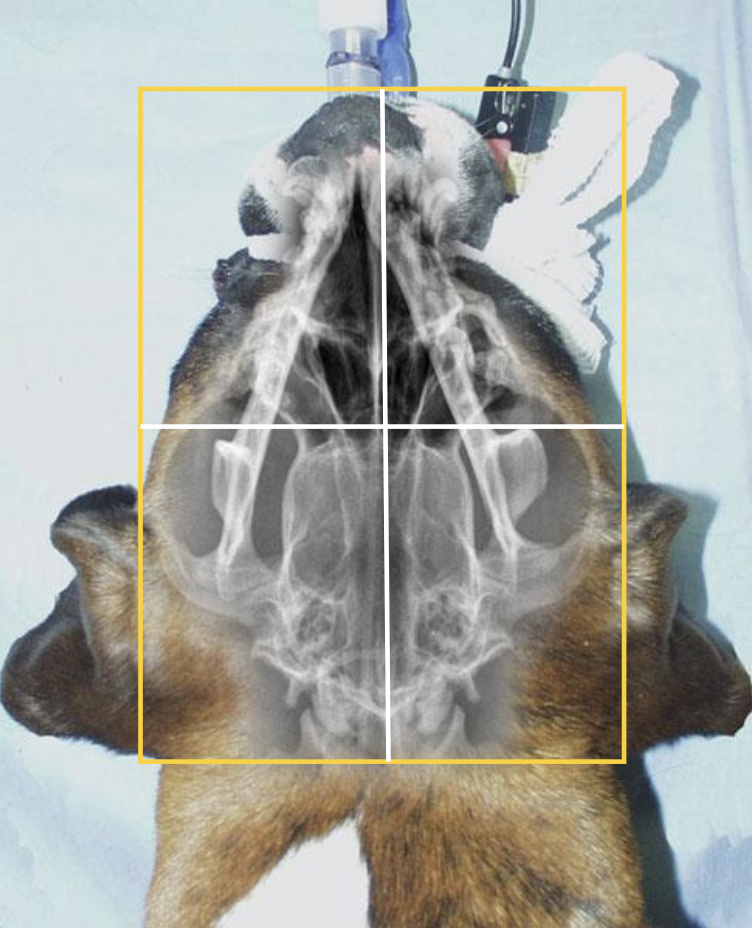

Vue dorso-ventrale

Indications :

- Cette projection permet d’évaluer le crâne, les arches zygomatiques, les os de l’oreille moyenne et interne et les articulations temporo-mandibulaires.

Positionnement :

- L’animal est en décubitus ventral.

- Apposer la tête bien à plat sur la table.

- S’assurer que la tête, le sternum et le thorax soient centrés et parallèles.

- S’assurer que les deux yeux soient parallèles entre eux et à la table.

Collimation :

- Rostralement, la collimation doit inclure le bout du nez.

- Caudalement, elle doit aller jusqu’à la protubérance occipitale.

- Latéralement, inclure les arches zygomatiques.

Centrage :

- Centrer le faisceau entre le bout du nez et la protubérance occipitale.

Orientation :

- S’assurer que la partie rostrale du crâne soitt vers le haut et la partie caudale soit vers le bas de l’écran.

- S’assurer que l’image est bien inversée, c’est-à-dire que la gauche de l’animal est à droite, et que la droite de l’animal est à gauche de l’écran.

Mesure :

- Une fois l’animal en position radiographique, placer la règle au point le plus large du crâne afin de prendre une mesure.